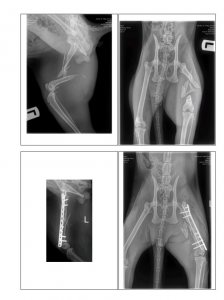

16.07.2022 Casi's Unfall… und nun auch noch Cosimo verletzt Beitrag #206 mennemaus Ehren-Mitglied Beiträge 24.139 Reaktionspunkte 17.737 Au wei, wenn man diese Fotos sieht, weiß man erst, wie schlimm die Verletzungen von Casi gewesen sind. Toll, dass die Ärzte es geschafft haben, die zerbröselten Knochen wieder zusammenzusetzen. Dein Casi hat richtig Glück gehabt, dass die Ärzte nicht amputiert haben, sondern dass sie die schwierige OP gewagt haben. Hoffentlich heilt das alles gut und hoffentlich bleiben keine Folgeschäden von dem Unfall übrig. Alles Gute für den kleinen Racker.

16.07.2022 Casi's Unfall… und nun auch noch Cosimo verletzt Beitrag #208 G Gast53073 Gast Unglaublich, wie toll die Ärzte das hinbekommen haben. Wie sauber die gearbeitet haben; die Nähte Und - die Röntgenbilder schauen denen meiner Patienten und meiner Mutter - abgesehen vom Schwanz - ziemlich ähnlich Alles Gute für den lieben Casi

16.07.2022 Casi's Unfall… und nun auch noch Cosimo verletzt Beitrag #209 Dextro Beiträge 8.316 Reaktionspunkte 8.811 Was ist denn mit den Splittern im Oberschenkel, die auf dem Bild mit der Platte noch so lose rumfliegen? Wachsen die von selbst an?

Was ist denn mit den Splittern im Oberschenkel, die auf dem Bild mit der Platte noch so lose rumfliegen? Wachsen die von selbst an?